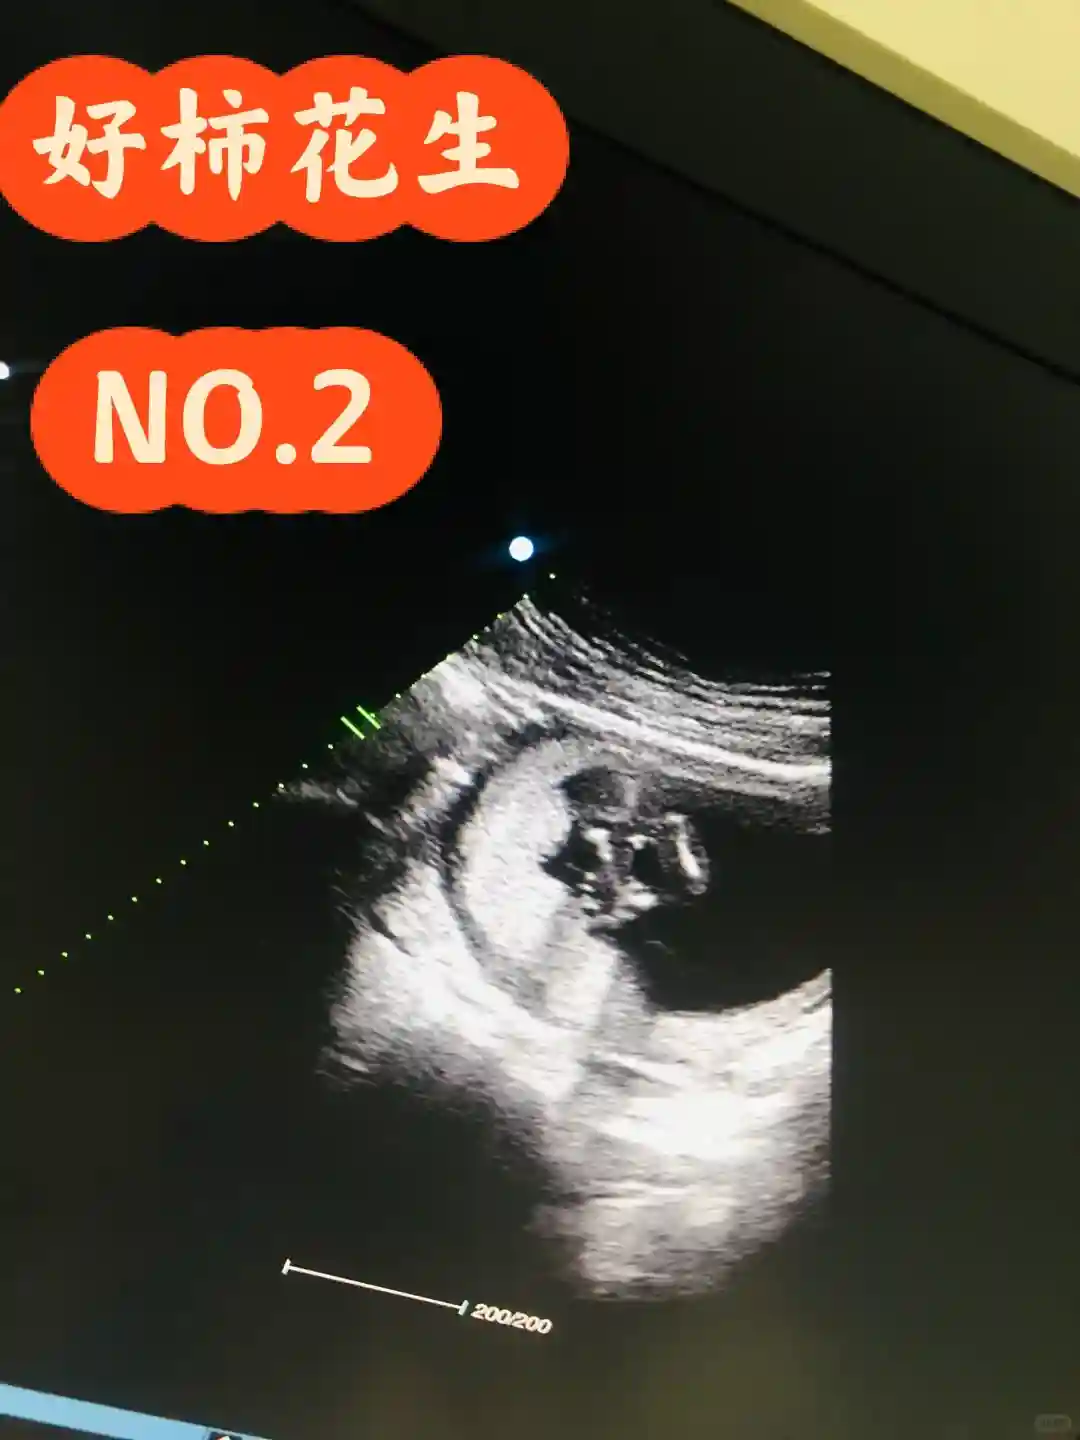

#彩超 #一个身体两个心跳2018年,尝试使用试管技术解决,在郑州市妇幼接受了二代试管技术的尝试,时至今日,依然后悔当时的决定。原因总结在结尾。有需要可以耐心往下看。选择三代试管技术是因为我作为男方,精子密度低,只能选择三代进行精子筛选后挑选合适的精子进行配型,其间,妻子接受了无数次抽血,化验,皮下注射肝素,黄体酮,妻子笑谈说自己快成刺猬了,看着她开玩笑,我很自责很内疚。经过大概三个月的周期,院方通知可以启动移植了,妻子接受人生第一次麻醉,移植开始,过程并不长,一小时左右。我在门口等待,如坐针毡。妻子出来后,麻醉尚有余威,絮絮叨叨和我神聊。她不知道,她说的都是幻境里面的内容,神魂尚未归位。回家等待14天后复查,当然,此次也未果。且让我对该院和试管技术产生了很大的抵触情绪。试管过程中大剂量的激素药物被注射进妻子体内,这次试管未果结束后,妻子身心都有较大影响,用了很长时间才得以恢复。(此次试管战况,妻子取出17个成熟卵泡,配对成功仅有三对,移植两个,剩余一个冷冻一年,一年后到院办理放弃冷冻)